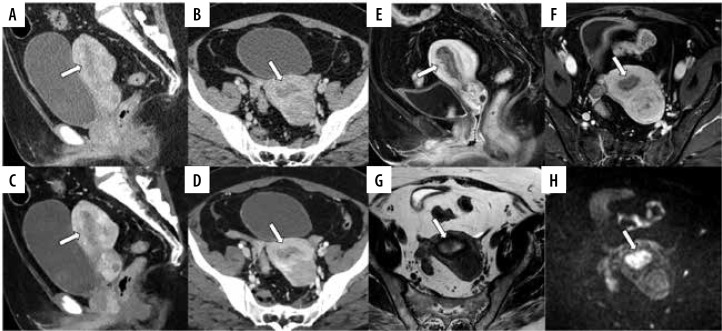

Material and methods: This retrospective study analysed 45 EC patients (mean age: 62 years, range: 44-84 years) undergoing contrast-enhanced CT with dual-energy CT (DECT) and MRI between September 2021 and October 2022. Dual-energy CT generated conventional CT (C-CT) and 40 keV VMI. Quantitative analysis compared contrast-to-noise ratio (CNR) of tumour to myometrium between C-CT and VMI. Qualitative assessment by 5 radiologists compared C-CT, VMI, and MRI for myometrial invasion (MI), cervical invasion, and lymph node metastasis. Sensitivity, specificity, accuracy, and area under the receiver operating characteristic curve (AUC) were calculated and compared for each diagnostic parameter.

Results: Virtual monoenergetic imaging showed significantly higher CNR than C-CT (p < 0.001) and a higher sensitivity for MI than C-CT (p = 0.027) and MRI (p = 0.011) but lower specificity than MRI (p = 0.018). C-CT had a higher sensitivity and AUC for cervical invasion than MRI (p = 0.018 and 0.004, respectively).

Conclusions: The study found no significant superiority of MRI over CT across all diagnostic parameters. VMI demonstrated heightened sensitivity for MI, and C-CT showed greater sensitivity and AUC for cervical invasion than MRI. This suggests that combining VMI with C-CT holds promise as a comprehensive preoperative staging tool for EC when MRI cannot be performed.